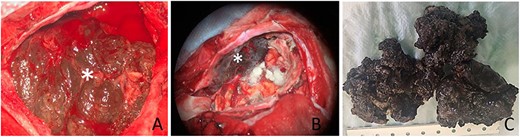

Surgical records reported a dark and highly vascular extra-axial tumor with a dural attachment to the left anterior skull base. The dura mater underlying the tumor surface was blackened (Fig. 2). The tumor extended throughout the subarachnoid space and invaded the cerebral parenchyma. In front of this strange aspect, the surgeon evoked a hemangioblastoma and could achieve a gross total resection with complete decompression of both optic nerves.

(A) Intra-operative appearance of the tumor (star); (B) aspect of dura mater after excision (star); (C) macroscopic appearance of the tumor after formalin fixation.

At pathological examination, the tumor was black, firm with irregular surface (Fig. 2C). Intra-operative smears revealed monomorphic and round tumor cells with basophilic characteristics. Some pigmented deposits were observed, but at this stage, the pathologist proposed the diagnosis of an undifferentiated round cell tumor (Fig. 3). Histologically—after formalin fixation—the tumor was composed of hypercellular sheets, nests and spindled cells associated with many melanic deposits. The tumor cells had a prominent nucleoli and a moderate amount of eosinophilic cytoplasm. We did not observe a significant nuclear pleomorphism or numerous atypical mitoses; however, we noted foci of tumor necrosis (Fig. 3).